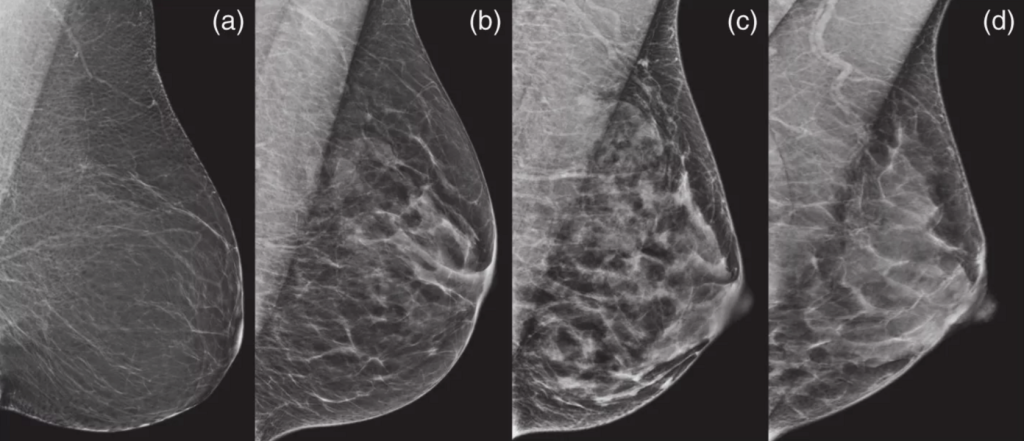

Birads 2 фкм 112 фотографий